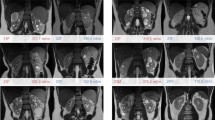

Representative coronal kidney images of noncontrast-enhanced steady-state free precession (SSFP) magnetic resonance imaging (MRI) with spatially selective inversion recovery pulse at 1.5-T unit (a, b, d–f) or conventional in-phase MRI at 3.0-T unit (c). a An SSFP image of a CKD G1 patient. b An SSFP image of a CKD G5 patient. c A conventional in-phase image of a CKD G1 patient. Minimal cortical thickness, cortical area, and medullary area are shown as a yellow band (d), blue area (e), and red area (f), respectively

A total of 107 patients diagnosed with CKD were enrolled in this study. Table 1 presents the background profiles of the entire study population. The median age was 64 years and 60.7% of the patients were men. The mean eGFR, raw eGFR, and 24-h creatinine clearance (Ccr) were 51.1 ± 22.7 mL/min/1.73 m2 (range 8.4–130.2), 53.7 ± 25.4 mL/min (range 7.6–118.6), and 67.6 ± 31.7 mL/min (range 4.0–179.0), respectively. The numbers and percentages of patients with each CKD stage were as follows: CKD G1, four (3.7%); G2, 35 (32.7%); G3, 48 (44.9%); G4, 13 (12.1%); G5, seven (6.5%). Anti-hypertensive agents were used in 93 (86.9%) patients, and 73 patients (68.2%) were treated with renin–angiotensin system (RAS) inhibitors, whereas 14 patients (13.1%) were treated with diuretics. Renal corticomedullary differentiation was clearly depicted in SSFP images using standard TI, but not in conventional IP images at even 3.0-T unit MRI (Fig. 1). The mean corticomedullary contrast ratio was higher in SSFP images than in IP images with some exceptional cases (Fig. 2), and the corticomedullary contrast ratio in SSFP images positively correlated with all of the three kidney functional parameters (Fig. 3). Then three morphological variables, minimal cortical thickness, cortical area, and medullary area of all patients were subjected to the validation study of interobserver reproducibility, and each ICC demonstrated a good correlation (Table 2). Average values of the measured kidney morphological parameters are shown in Table 3.

Our study revealed that renal corticomedullary differentiation was more clearly depicted in SSFP MRI with a spatially selective IR pulse than in conventional IP images, even in patients with CKD G4 and G5. This new imaging technique enabled us to measure the thickness or area of the each renal segment without contrast agents in patients with CKD and evaluate renal cortex atrophy.